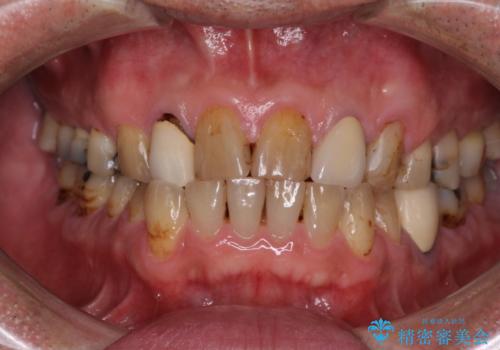

- コンポジットレジンやクラウンなど、様々な医院で治療を受けたために、統一感がなくなってしまった前歯を綺麗にしたいとのことで来院された患者様です。

黄ばんだ前歯や白すぎたクラウン、プラスチックの継ぎ接ぎなどを全てオールセラミッククラウンの統一感のある前歯に仕上げました。